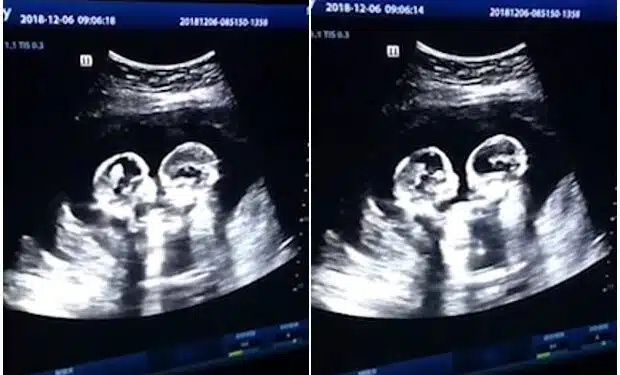

Μια έγκυος πήγε για το υπερηχογράφημα και όταν κοίταξε την οθόνη η καρδιά της “σταμάτησε”. Κανείς δεν μπορούσε να πιστέψει στα μάτια του.

Η 24χρονη μοιράστηκε τη στιγμή στο Facebook και από τότε έχει γίνει viral. Τι ήταν αυτό που άφησε τους πάντες άφωνους;

Η χαριτωμένη στιγμή που τα δίδυμα στην οθόνη πιάστηκαν να ανταλλάσσουν ένα φιλί. Στα 12 χρόνια καριέρας τους, οι γιατροί δεν είχαν ξαναδεί παρόμοιο υπερηχογράφημα. “Ήταν τόσο συναρπαστικό που τα είδαμε έτσι. Δεν φανταζόμουν ότι θα ήταν τόσο κοντά μαζί, αλλά ήταν και ήταν τόσο όμορφο αυτό που είδαμε”.

Στην αρχή, ένα μωρό φιλούσε το άλλο μωρό στο μάγουλο. Στη συνέχεια ήρθαν πιο κοντά και έδωσαν ένα γρήγορο φιλί στα χείλη. Η 24χρονη είπε ότι ήταν “τόσο χαριτωμένο”.

Είναι φανερό ότι αυτά τα μικροσκοπικά κορίτσια θα γίνουν οι καλύτερες φίλες στη ζωή και οι γονείς τους έχουν αποδείξεις γι’ αυτό!